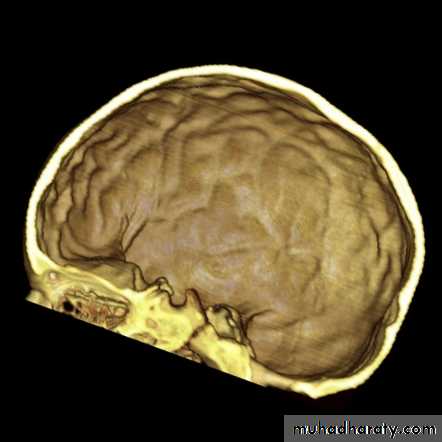

Skull X-ray findings in increased intracranial pressure

• Sutural separation in children.

• ‘Copper-beating’ marking of the cranial vault.

• Thinning of dorsum sellae.

• Erosion of the posterior clinoid process.

Copper-beating’ marking

Neurosurgery